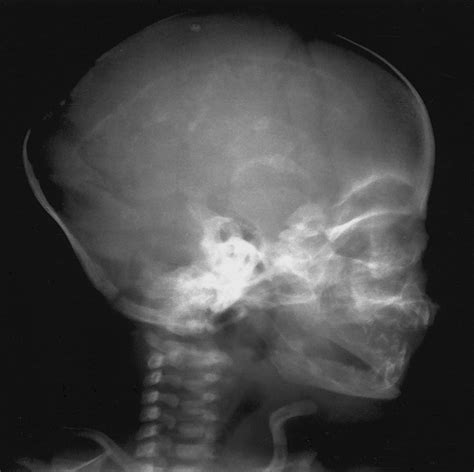

Several common findings can be identified through a Baby Skull Xray. Understanding these findings is essential for accurate diagnosis and treatment:

• Fractures: Visible cracks or breaks in the skull bones.

• Deformities: Abnormal shapes or structures of the skull.

• Infections: Signs of infection, such as bone erosion or swelling.

• Tumors: Abnormal growths or masses within the skull.

• Developmental Abnormalities: Issues with the development of the skull, such as premature fusion of sutures.

Each of these findings requires a different approach to treatment and care. Healthcare providers will use the X-ray results to develop a tailored plan for the baby’s health and well-being.